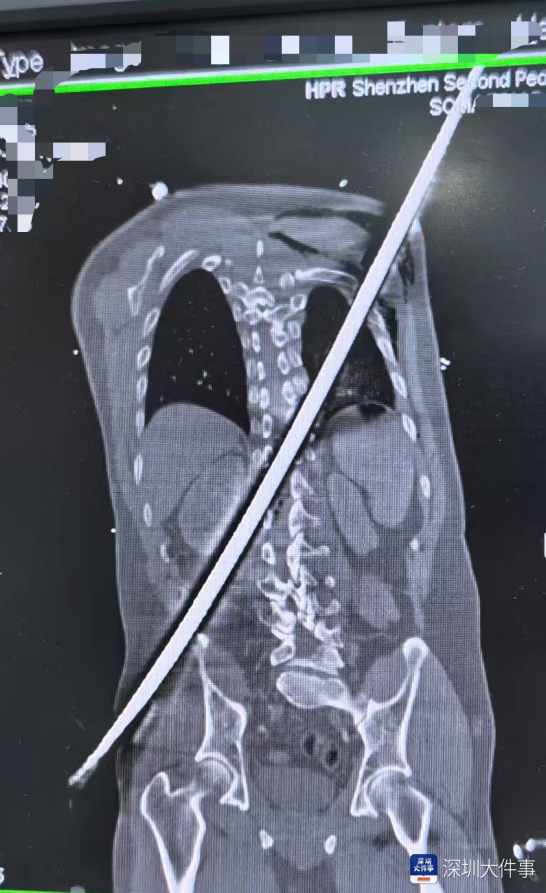

医院急诊科第一时间启动抗休克治疗,快速稳定患者血压,同步完善各项检查,为后续治疗筑牢基础、抢占先机。全身CT扫描精准勾勒出钢筋在体内的“行走路径”——

钢筋险之又险地穿过腹膜后间隙,击穿胸腰段脊柱椎管,最终穿入胸腔,其路径紧贴肾脏、大血管等关键脏器——每一次心跳,都可能让钢筋锋刃与血管发生摩擦,引发灾难性大出血。